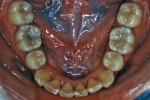

| マルチブラケット終了時